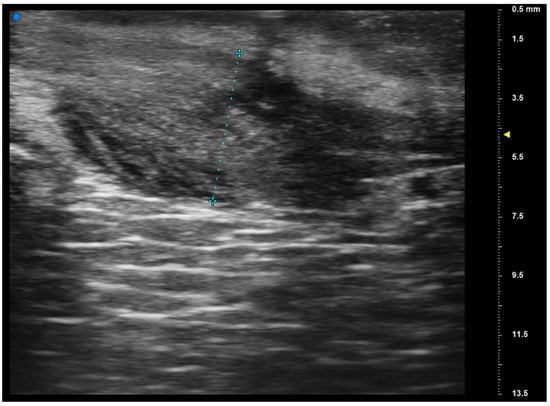

Reliability of Ultrasonographic Assessment of Depth of Invasion and Tumor Thickness in Intraoral Mucosa Lesions: A Preliminary Experience

2.2. UHFUS Scan Protocol